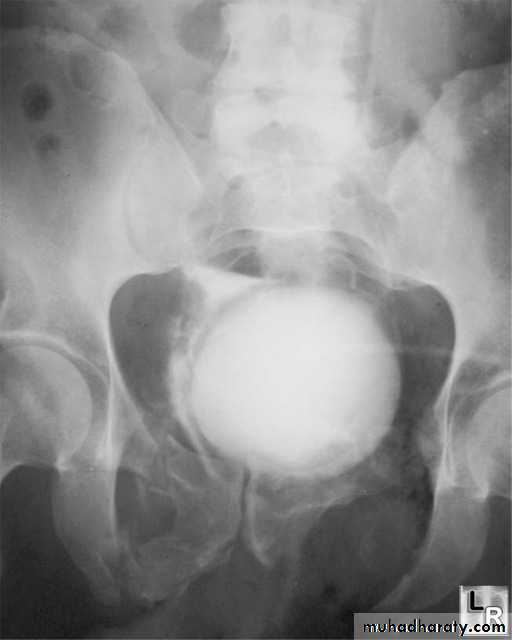

Urinary bladderThe bladder is well demonstrated on all imaging modalities. At US, the simplest routine method of imaging, the bladder lumen should be free of echogenic structures and it's wall should be of uniform thickness. When the bladder is distended, the wall should be less than 3 mm thick. The volume of the bladder may be calculated by measuring the dimensions of the bladder

• 1.incomplete bladder emptying(normally, there should be no residual urine)

• 2.increased thickness of the bladder wall

• 3.trabeculation: undulated inner side of the bladder wall due to prominent muscles strands(muscular hypertrophy), these are well seen on US and IVU

• 4.Sacculations and diverticulae formation: they are focal herniation of the urothelium and submucosa through week sites in the bladder wall. Small protrusions called sacculations and as they enlarged above 2 cm, they called diverticulae. They can be seen on US, IVU and CT.

• 5.in severe cases, there may be dilatation of the ureters and hydronephrotic changes in the kidneys.